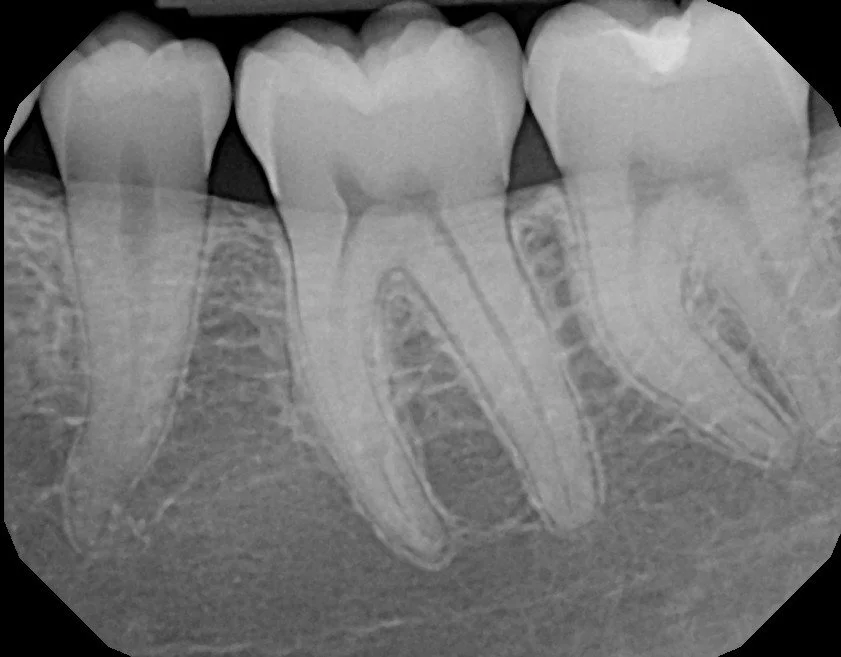

Limited exams, treatments, and extractions can be offered on short notice for toothaches, infections, and broken teeth.